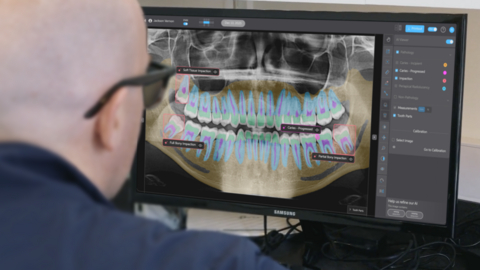

Pearl’s Second Opinion real-time chairside pathology detection platform is now FDA cleared to identify and highlight suspected caries, periapical radiolucencies, and impacted third molars on panoramic radiographs.

Pearl’s Second Opinion real-time chairside pathology detection platform is now cleared to identify and highlight suspected caries, periapical radiolucencies, and impacted third molars on panoramic radiographs. Panoramic radiographs present a broad anatomical view that can reveal a wide range of dental and maxillofacial conditions—but their complexity and anatomical distortion can make consistent and accurate pathology detection difficult. This latest FDA clearance validates the performance of Pearl’s radiologic AI applied to one of dentistry’s most diagnostically challenging imaging formats.

“Panoramic x-rays are increasingly popular because they capture the full mouth with lower radiation than a traditional full-mouth x-ray series, but they remain one of the hardest types of dental x-ray to read reliably,” said Ophir Tanz, founder and CEO of Pearl. “AI brings greater clarity and certainty to pano interpretation. Patients benefit as well: Diagnoses are easier to understand when findings are clearly highlighted and labeled. Although panoramic x-ray adoption in the U.S. still trails the U.K. and Europe, this FDA clearance affirms the strength of our technology and moves the industry closer to universal AI support across dental radiology.”